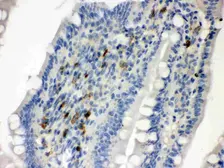

NP_002990

Images